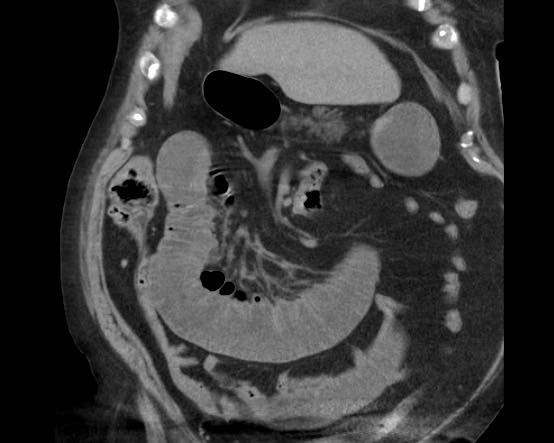

Đây là hình ảnh điển hình của tắc ruột do sỏi mật.

Lưu ý mức độ khó khăn khi phát hiện viên sỏi không vôi hóa.